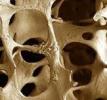

Osteoporosi, ancora oggi è difficile riconoscerlaNonostante alcuni sintomi siano inconfondibili, nella maggior parte dei casi l’osteoporosi risulta asintomatica. Ecco perché è importante sottoporsi a controlli preventivi a partire dai 30 anni Sono oltre 200 milioni le persone nel mondo affette da osteoporosi, ma nonostante ciò questa condizione molto spesso non viene riconosciuta o non si riesce a diagnosticarla a causa della sua asintomaticità. La maggior parte delle persone infatti, scopre di essere...

Prevenire osteoporosi

Una donna su quattro superati i 40 anni, può soffrire di osteoporosi. Dopo i 60 anni ne soffre una donna su tre e dopo gli 80 anni la metà delle donne ne è affetta. L’osteoporosi non è un disturbo esclusivamente femminile, ne soffrono anche gli uomini. Questa malattia crea un aumento delle possibilità di fratture, in quanto le ossa diventano molto sottili e anche cadute leggere possono determinarne rotture.